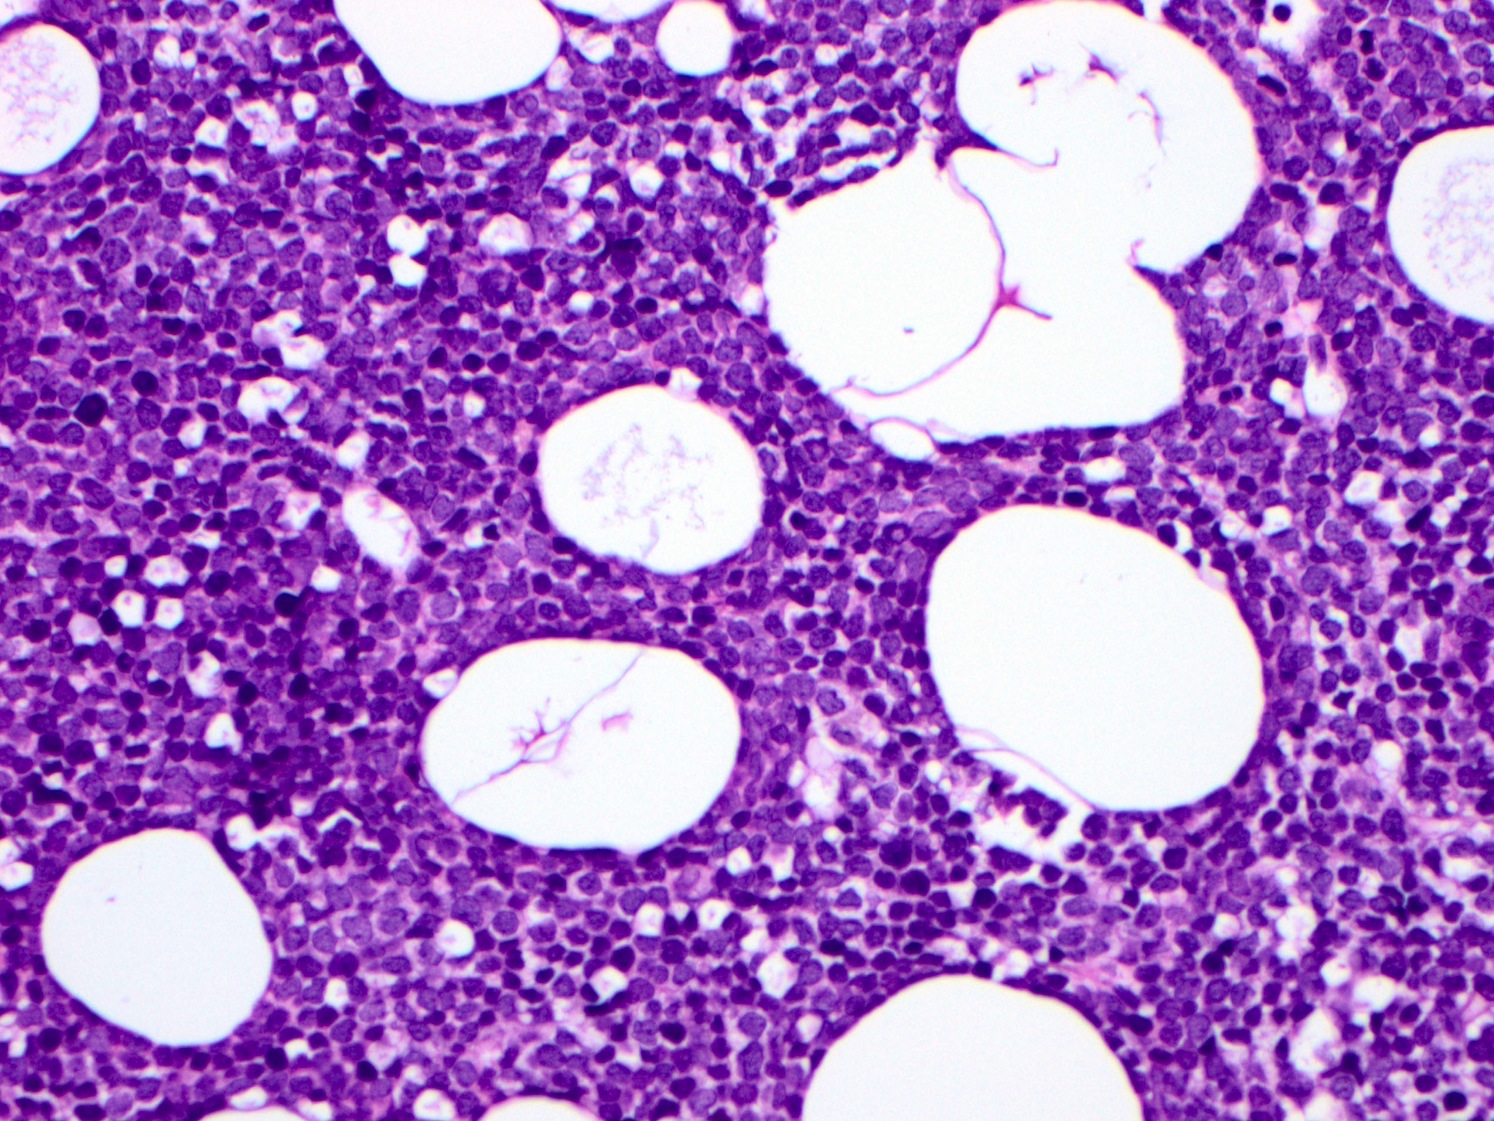

Microscopic (histologic) description

- Blastoid variant

- The growth pattern is usually diffuse

- Less frequently nodular pattern

- Starry sky appearance common in low power

- Intermediate sized cells

- Monotonous population

- Immature chromatin

- Scant cytoplasm

- High mitotic rate > 20 - 30/10 high power fields

- Resembles, in part, lymphoblastic lymphoma

Microscopic (histologic) images